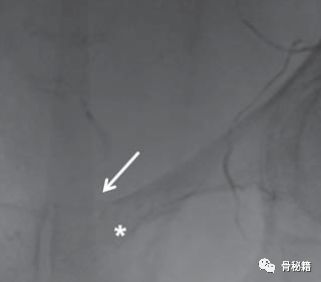

行CT,发现腹腔有10*10*15的血肿位于耻骨骨折旁边。

行血管造影后确定了为死亡之冠出血,后行血管栓塞闭孔动脉后,出血停止。一周后康复出院。